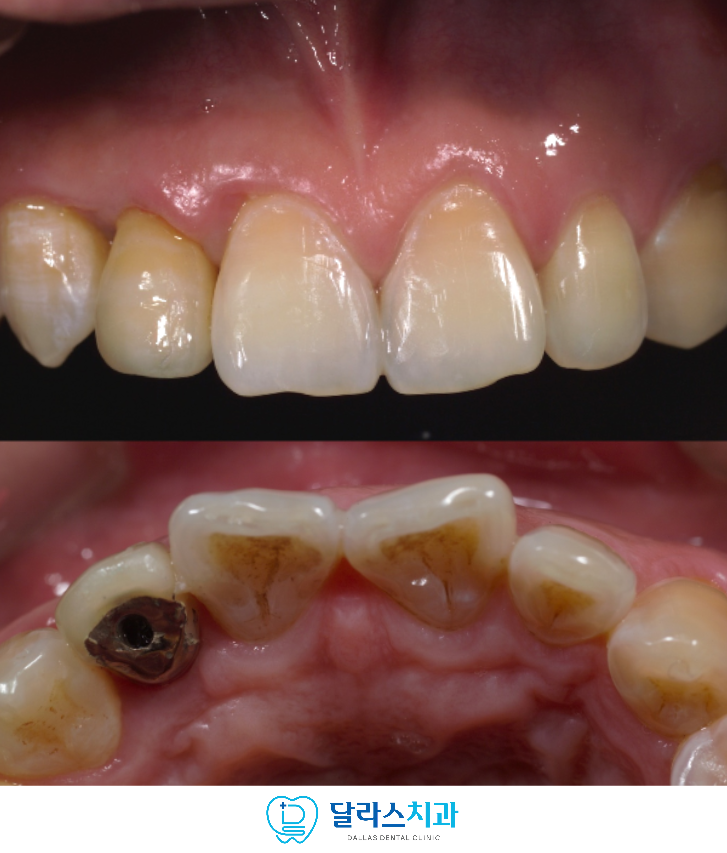

마지막 단계에서 임플란트를 보철 수복을 완료하였으며

환자분은 심미성과 기능 모두에서 만족스러운 결과를 경험하셨습니다.

노원치과에서는

보철물에는 작은 스크류 홀이 있는 타입으로 제작을 하여

필요할 때 보철물을 스크류로 풀어 제거할 수 있습니다.

겉에서 보기에는 완전하게 장착되어 깔끔하지만 문제가 발생하였을 때

유지,보수를 필요로 할 때에는 분리 가능하다는 장점이 있습니다.